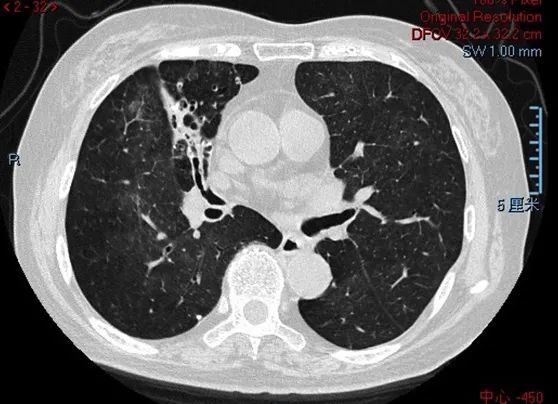

胸部CT(2021-1-13)

胸部CT(2021-1-25)

胸部CT(2021-2-23)